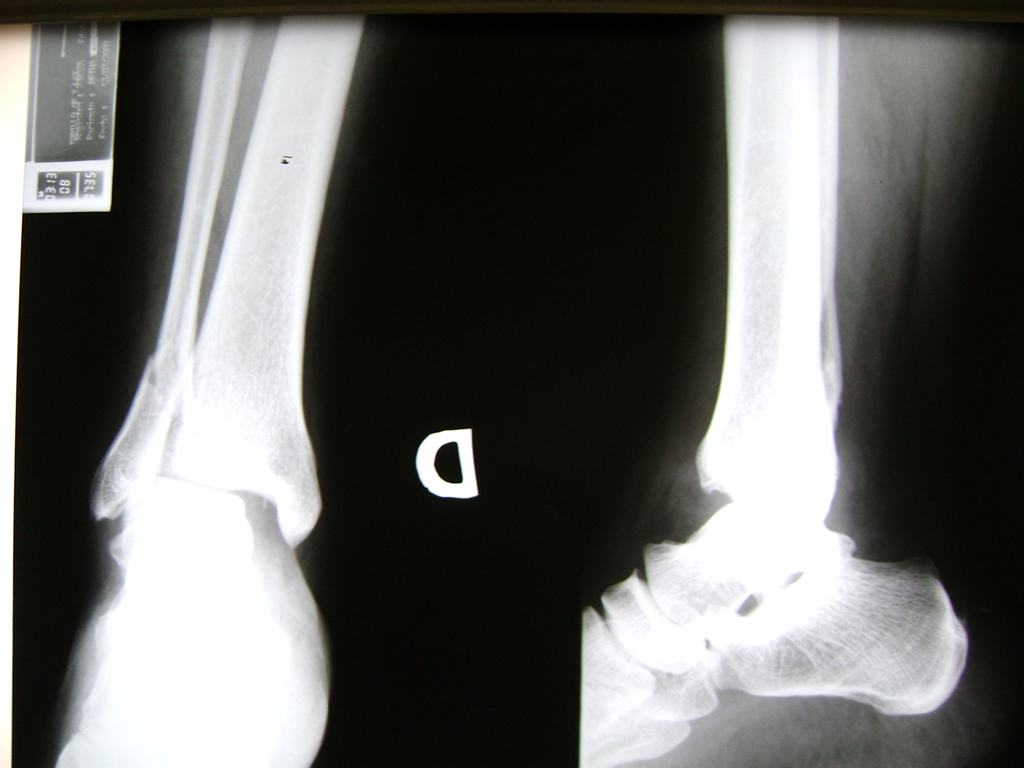

Una fractura de tobillo es la rotura de uno o más de los huesos del tobillo. Estas fracturas pueden ser:

- Parciales (el hueso está sólo parcialmente fisurado, no del todo).

- Completas (el hueso está perforado y está en 2 partes).

Algunas fracturas de tobillo pueden requerir cirugía si:

- Los extremos de los huesos están desalineados entre sí (desplazados).

- Los tendones o ligamentos (tejidos que sujetan los músculos y los huesos entre sí) están rotos.